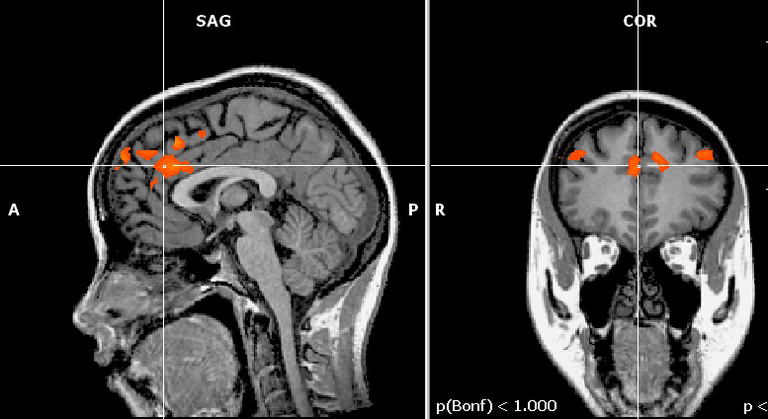

Brain activity when people exert self-control.

But Hedgcock’s study is the first to actually show it happening in the brain using fMRI images that scan people as they perform self-control tasks. The images show the anterior cingulate cortex (ACC)—the part of the brain that recognizes a situation in which self-control is needed and says, “Heads up, there are multiple responses to this situation and some might not be good”—fires with equal intensity throughout the task.

However, the dorsolateral prefrontal cortex (DLPFC)—the part of the brain that manages self-control and says, “I really want to do the dumb thing, but I should overcome that impulse and do the smart thing”—fires with less intensity after prior exertion of self-control.